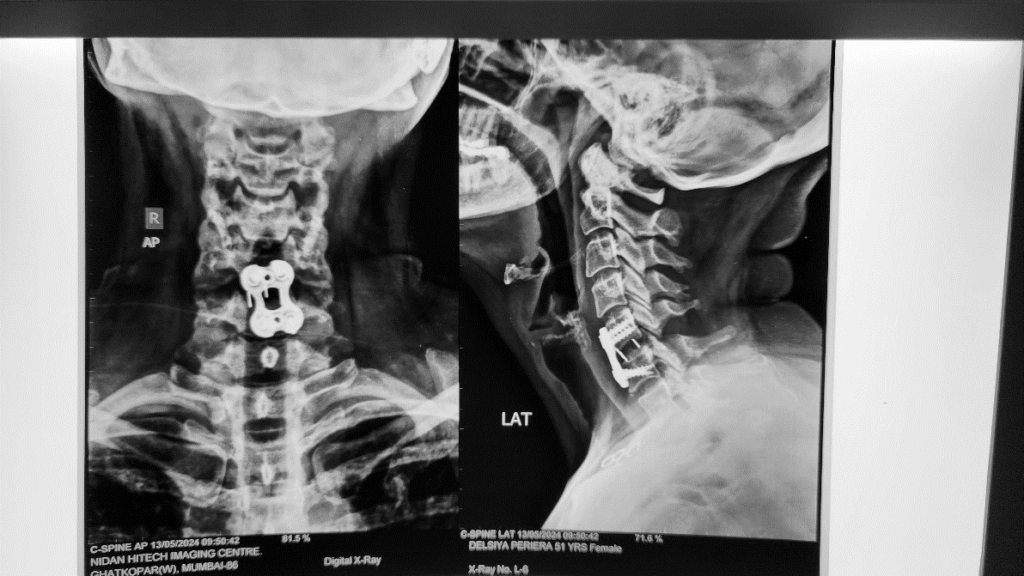

X-ray Cervical spine showed no much abnormalities. (Pic 1)

She underwent Anterior cervical decompression and instrumentation.

Pic 1- No much abnormalities